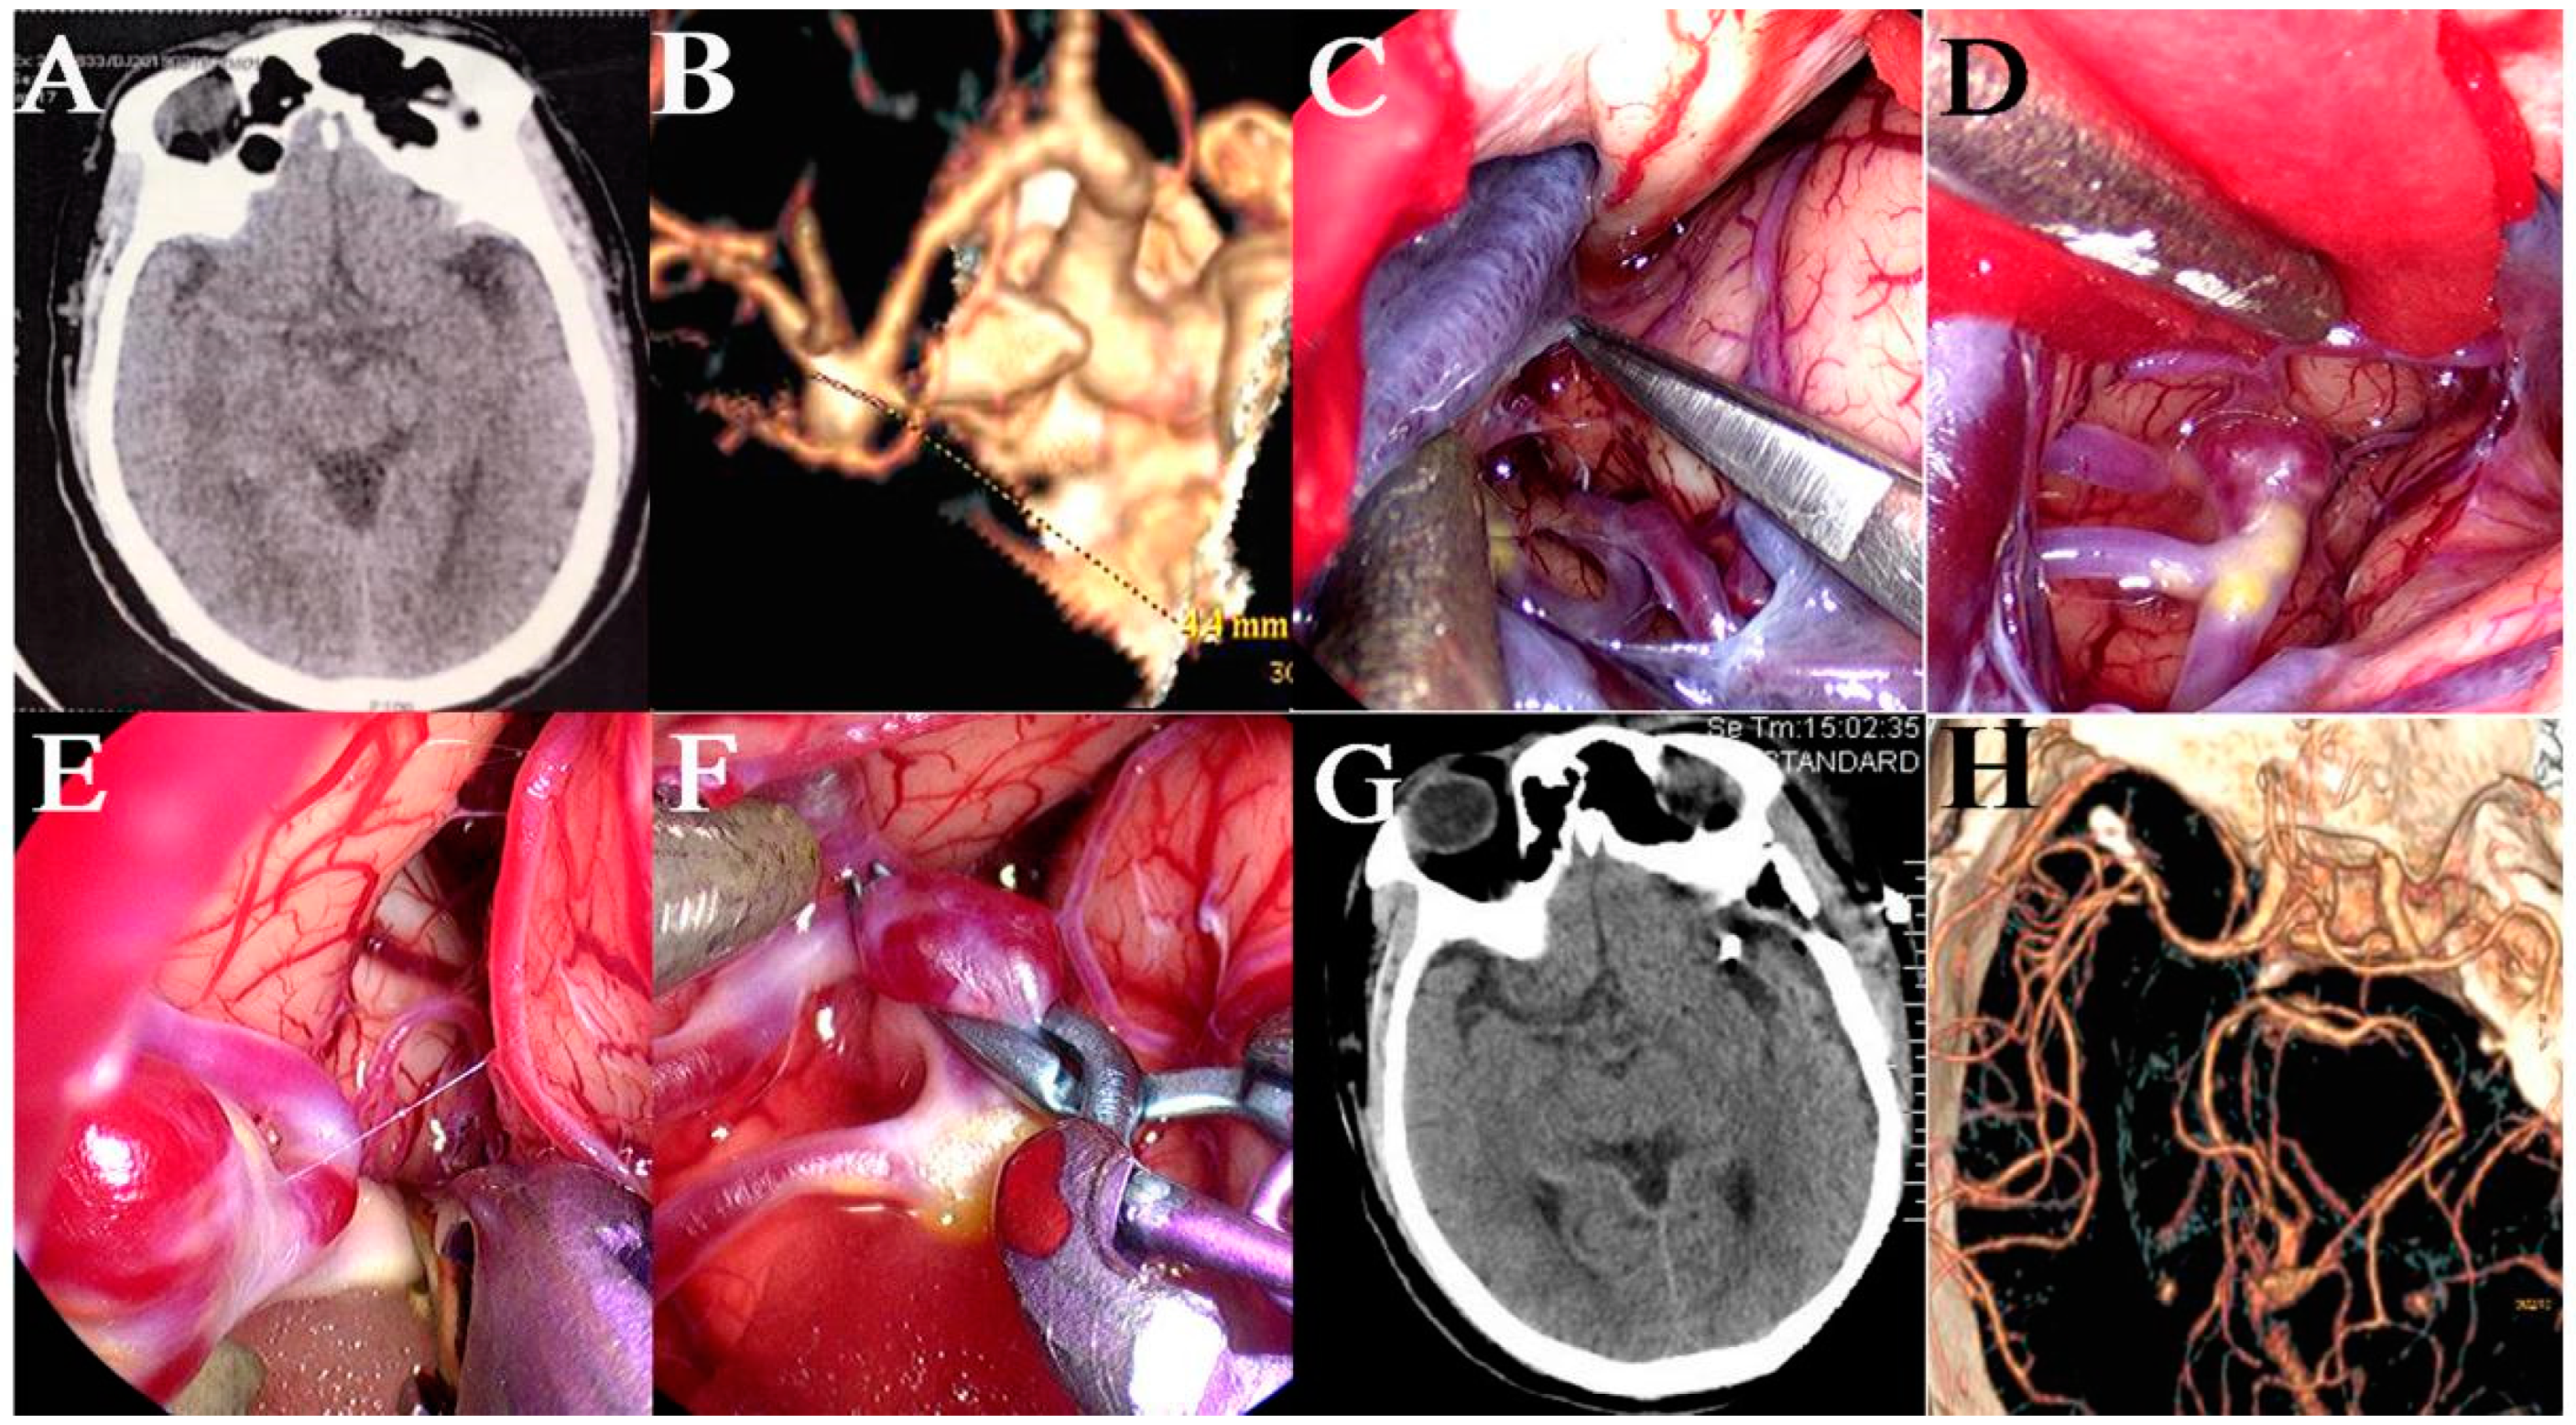

Surgical Clipping of Intracranial Aneurysms Using a Transcranial Neuroendoscopic Approach

2.3. Surgical Procedures